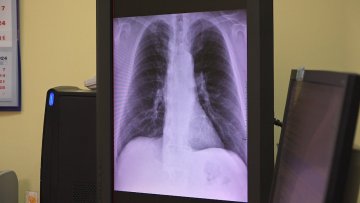

Иако туберкулоза није ствар прошлости, она је се јавља веома ретко. До тога је довела комбинација мера: имунизација бесеже вакцином одмах по рођењу, благовремена дијагностика и адекватно лечење, објашњава пулмолог, др Елизабета Врана. У ризику од обољевања су старије особе које су имунокомпромитоване, прецизира докторка, али напомиње да је болест углавном излечива.

„Најчешче оболевају особе старије животне доби и мушкарци, они који имају ослабљен имунитет, попут оболелих од ХИВ-а или су алкохоличари, можда живе у лошијим социо-економским условима, не хране се како треба. Међутим, ми када поставимо дијагнозу прописујемо терапију која се најчешће састоји у прва четири месеца од четири лека, и следећа четири месеца, пацијент пије шест таблета и најчешће долази до излечења,“ наводи др Врана.